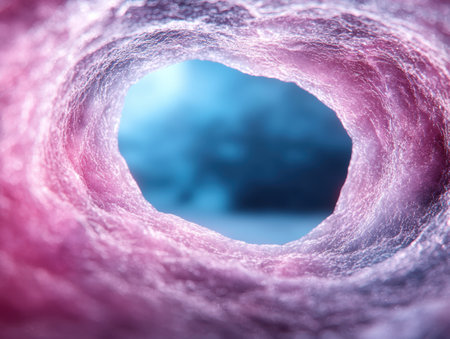

Cross-section esophagus of the dog. Medical teaching equipment and biological tissue slide. Educational material for the study and treatment of doggy. Colouring with hematoxylin and eosin.

science medical anthropotomy physiology micrograph of blood vessel, artery and vein.